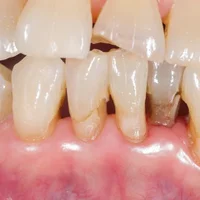

Gingivale (rétraction des gencives)